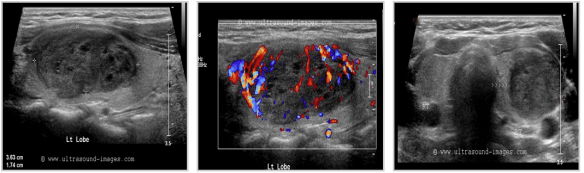

Pics form ultrasound-images.com :

ADENOMAS

thyroid_adenomatous nodules thyroid_follicular adenoma